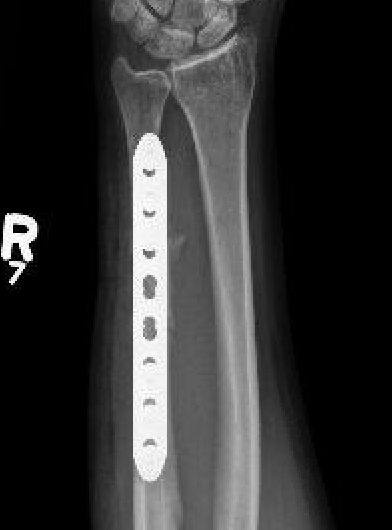

Operative management

Indications

Acute fractures

- > 50% displacement

- > 10 degrees angulation

- midshaft ulna fractures - higher risk of nonunion

Options

Compression plating

Technique